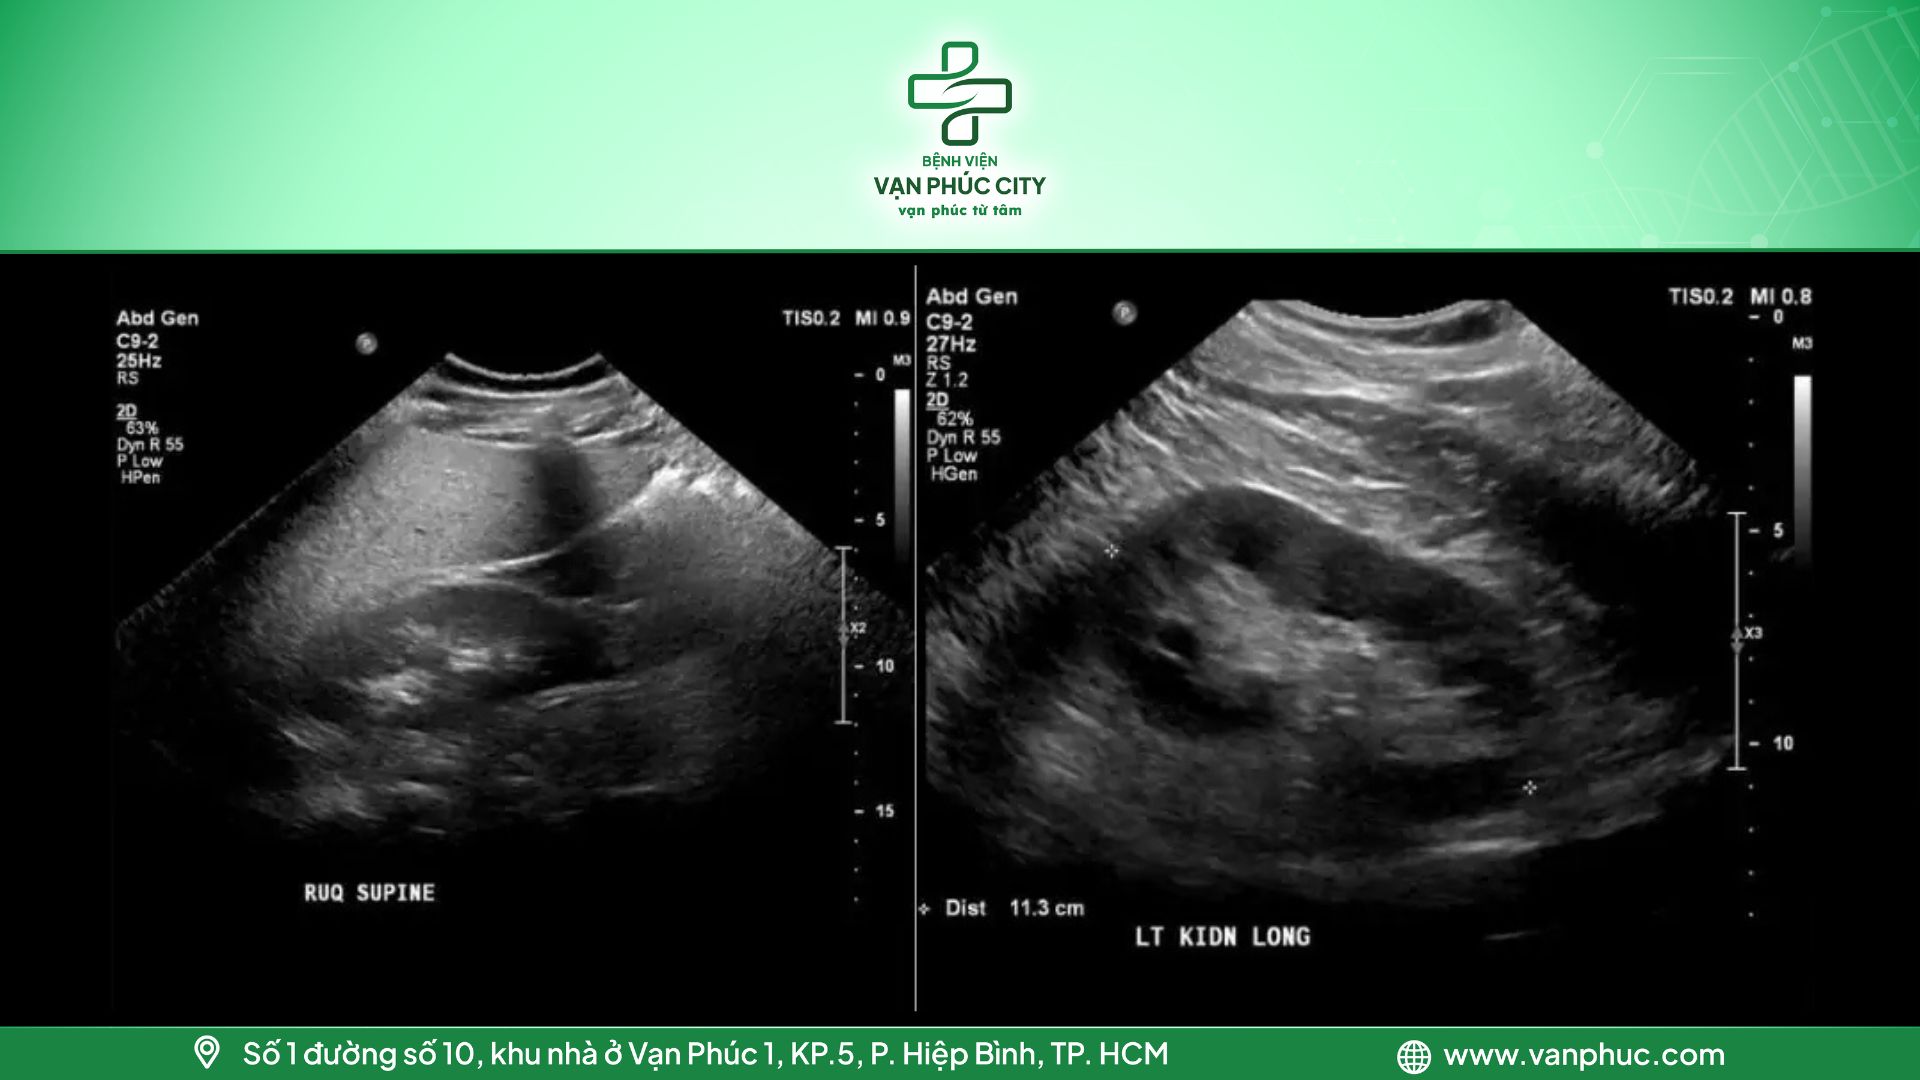

2.3. Gan nhiễm mỡ cấp độ 3

Khi lượng mỡ trong gan vượt quá 30%, đây là dấu hiệu của tình trạng gan nhiễm mỡ nghiêm trọng. Kết quả siêu âm cho thấy hình ảnh hồi âm lan tỏa tăng mạnh, kèm theo hiện tượng hút âm vượt mức bình thường. Điều này khiến vùng cơ hoành và các đường tĩnh mạch không còn rõ ràng, gây khó khăn trong việc xác định cấu trúc gan qua hình ảnh siêu âm.

Hình 4: Gan nhiễm mỡ cấp độ 3

2.4. Gan nhiễm mỡ khu trú

Trong một số trường hợp, gan nhiễm mỡ có thể tích tụ không đồng đều trong tế bào gan, được gọi là gan nhiễm mỡ không đồng nhất. Đây là hiện tượng mà một số vùng trong gan có tỷ lệ mỡ tích tụ cao hơn, trong khi các vùng khác lại có lượng mỡ ít hơn hoặc không có mỡ. Điều này dẫn đến sự khác biệt rõ rệt về mật độ và cấu trúc, tạo ra hình ảnh siêu âm với sự phân bố tăng âm và giảm âm, giống như một bản đồ giữa các vùng trên bề mặt gan.